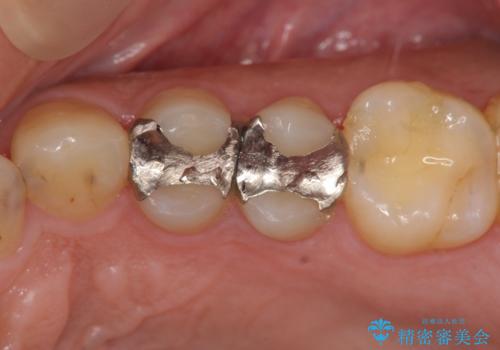

- 近所の歯医者で銀歯を入れたところ噛み合わせも悪く、毎回食べ物が詰まり困るとのことで来院されました。

X線写真より歯と適合の悪い銀歯が装着されていたので、除去し耐久性・削る量の少なくて済むゴールドインレーで再修復を行います。

ゴールドは化学的に安定し壊れることの少ない材料です。また薄く加工できるため歯を削る量もセラミック治療に比べ少なくすることができます。